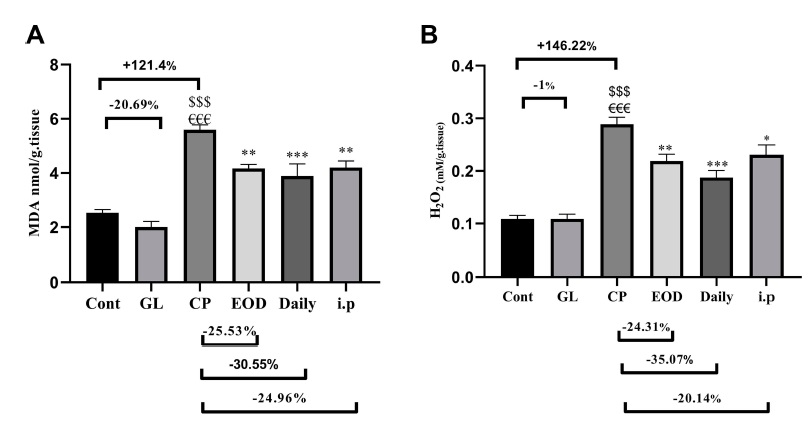

This article further compares the oxidative damage suffered by each group of liver tissues. There are two observation indicators: MDA (malondialdehyde), a product formed after the destruction of cell membranes by free radicals, and H2O2 (hydrogen peroxide), an intermediate product formed after the metabolism of free radicals by antioxidant enzymes.

Both of these products have the oxidative properties of free radicals and must be further treated before they can be truly “detoxified”, so the amount of them can tell us the oxidative damage that the liver tissue “has suffered” and “will suffer”.

Obviously, cisplatin will cause great oxidative damage to liver tissue, but if Ganoderma lucidum is involved In treatment at the same time, such damage can be reduced (Figure 3).

Because the changes in the concentration of antioxidant enzymes (SOD and GSH) in the liver tissues of each group and the changes in oxidative damage indicators showed a completely opposite trend, it can be inferred that Ganoderma lucidum will increase the antioxidant capacity of liver tissue and reduce the damage by “increasing antioxidant enzymes”.

Figure 3 Effects of cisplatin and Ganoderma lucidum on oxidative damage of liver tissue